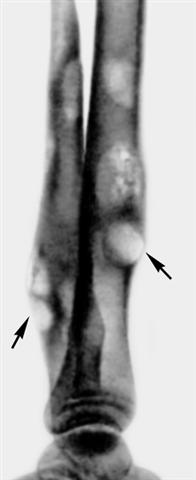

Рис. 1. Рентгенограмма костей голени ребенка 13 лет при гуммозном периостите (боковая проекция): гладкие, ровные периостальные наслоения вокруг гумм (указаны стрелками).